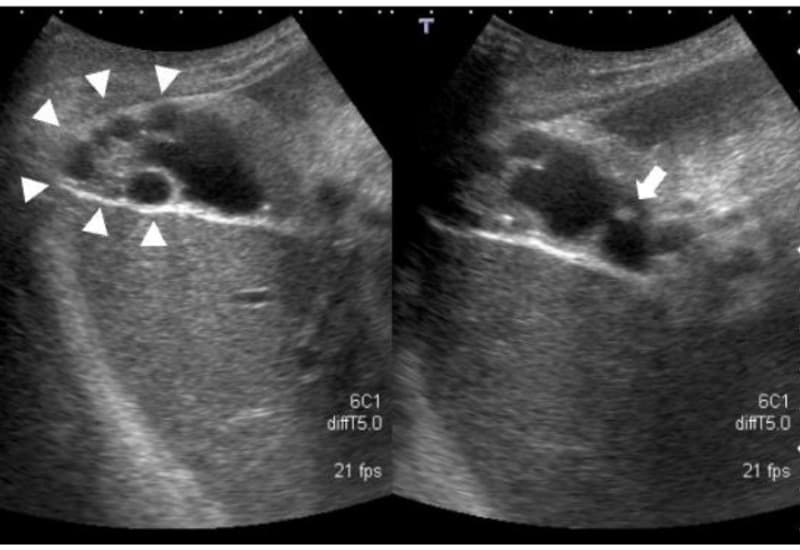

Tổn thương có thể khu trú ở một đoạn thành túi mật hoặc lan tỏa toàn bộ. Trên siêu âm, bác sĩ có thể thấy thành túi mật dày, không đều, kèm các hốc nhỏ dạng nang trong thành. Dấu hiệu “đuôi sao chổi” do phản xạ từ tinh thể cholesterol là hình ảnh gợi ý điển hình. Trong một số trường hợp, người bệnh có thể kèm sỏi túi mật.